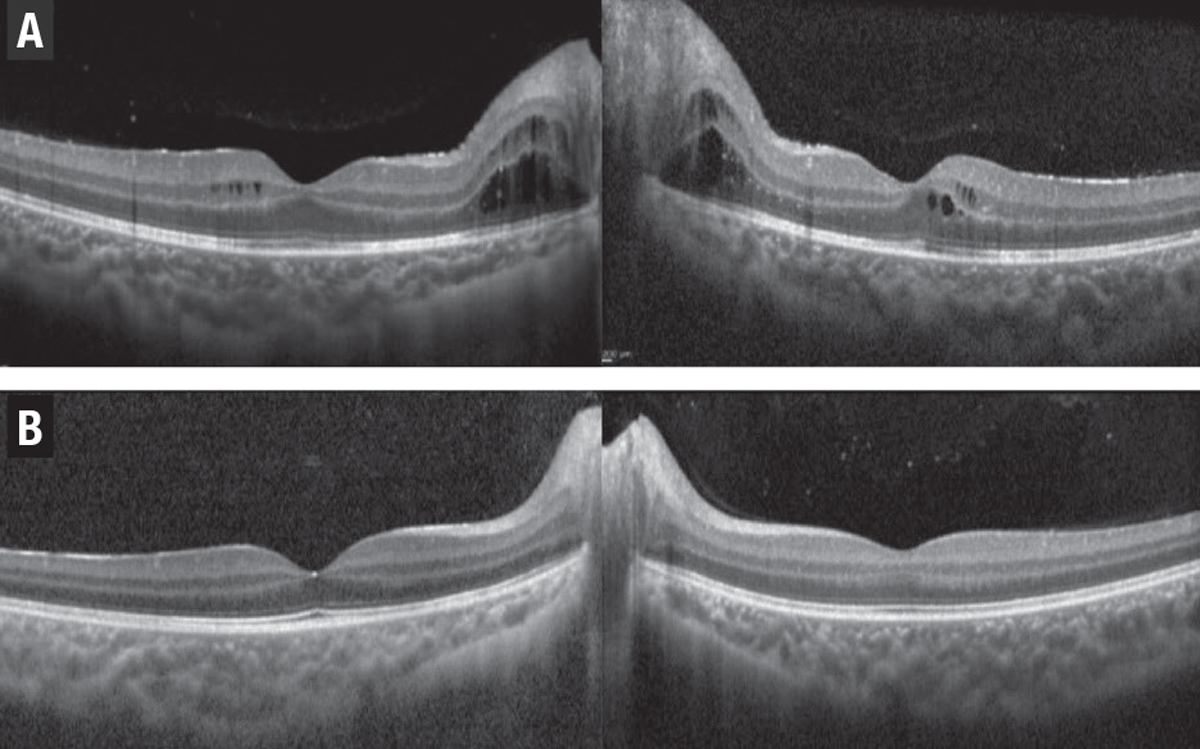

| Figure 1. A) A 68-year-old woman with a history of sarcoidosis presented with leakage and uveitic macular edema (UME) in the left eye. B) After treatment with intravitreal triamcinolone acetonide, the UME resolved six weeks later. |

- Dexamethasone 0.7-mg implant. It’s approved for intravitreal use in patents with uveitis and the effect lasts for three to six months. The POINT trial of Ozurdex (Allergan/AbbVie), a prospective randomized clinical study with intravitreal and periocular triamcinolone, showed that both intravitreal steroids are more potent than the periocular steroid in controlling UME and improving visual acuity, with a modest increase in intraocular pressure. No statistically significant difference was found between the two intraocular steroids9 (Figure 1).